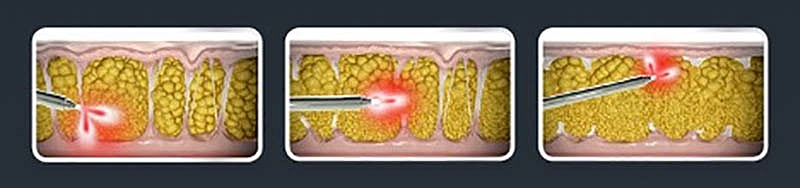

The two types of liposuction treatments are Tumescent Lipo and Super-Wet lipo. Dr. Durkin will discuss these procedures in more detail during your consultation.

There are many procedures to choose from at Ocean Drive Plastic Surgery. Regardless of the type of procedure used, Dr. Durkin favors the tumescent liposuction or super-wet liposuction techniques. This essentially means applying a large amount of wetting solution before attempting to break up and extract the fat. Over the years, he has found this technique provides a superior aesthetic outcome. It also tends to enhance patient comfort and allow for maximum fat reduction compared to wet or dry techniques.

While trying to make sense of your options, it is helpful to know that technology refers to a specific tool or device, while a technique is how a surgeon uses the device. With that in mind, here are some terms worth knowing:

The wetting solution in the tumescent Lipo approach causes the fat deposits to swell once injected. Once the excess fat increases in volume, it makes it easier to move around and remove it.

Power assist refers to how the cannula moves as it breaks down the fat. Instead of an aggressive back-and-forth motion, the power-assist cannula vibrates rapidly. The vibrations help to liquefy the fat cells with ease. The process is gentler on the tissues and takes less time, which benefits the patient and surgeon.

He then injects a wetting solution (tumescent fluid) into the treatment site. The solution contains saline and epinephrine to minimize bleeding, bruising, and discomfort. He then makes one or more tiny incisions through which he passes a cannula. The cannula separates the fat cells so a vacuum-assisted suction cannula can easily remove them.